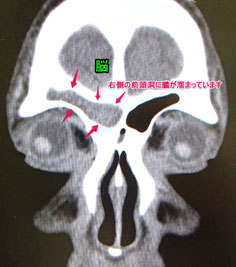

この患者さんは、右眼の上の持続的な痛みで受診された方です。

頬や目の内側、奥、おでこの部分に4つの副鼻腔という空洞があります(→副鼻腔炎とは

この方は前頭洞という前額部の奥の空洞とお鼻の間の交通路がつまっており、前頭洞の中に膿がたまった前頭洞炎を起こしていました。